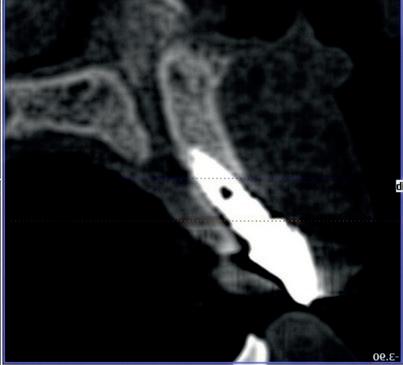

Implantologische behandelingen in het esthetische front vragen meer dan technische vaardigheid alleen. Ze vragen om overzicht, timing, vertrouwen en een team dat als vanzelf samenwerkt onder druk. Juist bij complexe casussen, waarin angst, infectie en hoge esthetische verwachtingen samenkomen, wordt zichtbaar hoe bepalend de rol van de tandartsassistent is.

Deze casus beschrijft een uitgebreide immediate implantaatbehandeling bij een patiënt die door meerdere collega’s werd geweigerd. Niet omdat de mogelijkheden ontbraken, maar omdat de complexiteit vroeg om een perfect afgestemde samenwerking. Het verhaal laat zien hoe de assistent in zo’n traject veel meer is dan een uitvoerende kracht of “mal”, maar een dynamische surgical guide die het proces mede stuurt, bewaakt en mogelijk maakt.De patiënt: wanneer alles samenkomt

De basis van een complexe beslissing

Mijn behandelplan begint altijd met een uitgebreid klinisch onderzoek. Dat omvat een medische anamnese, intra- en extra-orale camerafoto’s en uitgebreid verwachtingsmanagement. In deze fase is mijn assistent vooral bezig met het zorgvuldig vastleggen van alle gegevens. Juist dat nauwkeurig documenteren zorgt voor rust in de behandelkamer. Minstens zo belangrijk is het luisteren naar de patiënt. Niet alleen naar de klachten, maar naar het

4. Pre-chirurgische OPG.

levensverhaal en de mens achter de brug. Begrijpen wat deze behandeling voor iemand betekent, is cruciaal voor het uiteindelijke succes.

Na het klinische onderzoek volgde het röntgenologisch traject. De CBCT liet precies zien wat we al vreesden: een front waarin het bot onregelmatig was, duidelijke radiolucenties rond de pijlers en een infectiegebied dat zich onder vrijwel de gehele brug had verspreid. Tegelijkertijd was er ook potentie. Net voldoende botstructuur om immediate implantaatplaatsing te overwegen, mits alles perfect gepland zou worden.